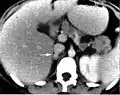

درمان فئوکروموسیتوما شامل ابتدا کنترل فشار خون بالا با داروهای کاهنده فشار خون (مانند فنوکسی بنزامین و لابتولول) است.فنتولامین داروی انتخابی درمان فئوکروموسیتوما است. هنگامیکه فشار خون تحت کنترل است، درمان این بیماری برداشتن غده آدرنال غیرطبیعی توسط جراحی (لاپاراسکوپی یا لاپاراتومی) است. فنوکسی بنزامین را ۱۴-۱۰روز قبل از عمل برای بیماری شروع میکنند که دوز اولیه معمول این دارو mgr 10 هر ۱۲ ساعت است و سپس هر چند روز یکبار mgr 20-10 به آن اضافه میشود تا فشار خون کنترل شود. برای مشخص کردن محل توده از CTscan یا MRI استفاده میشود.